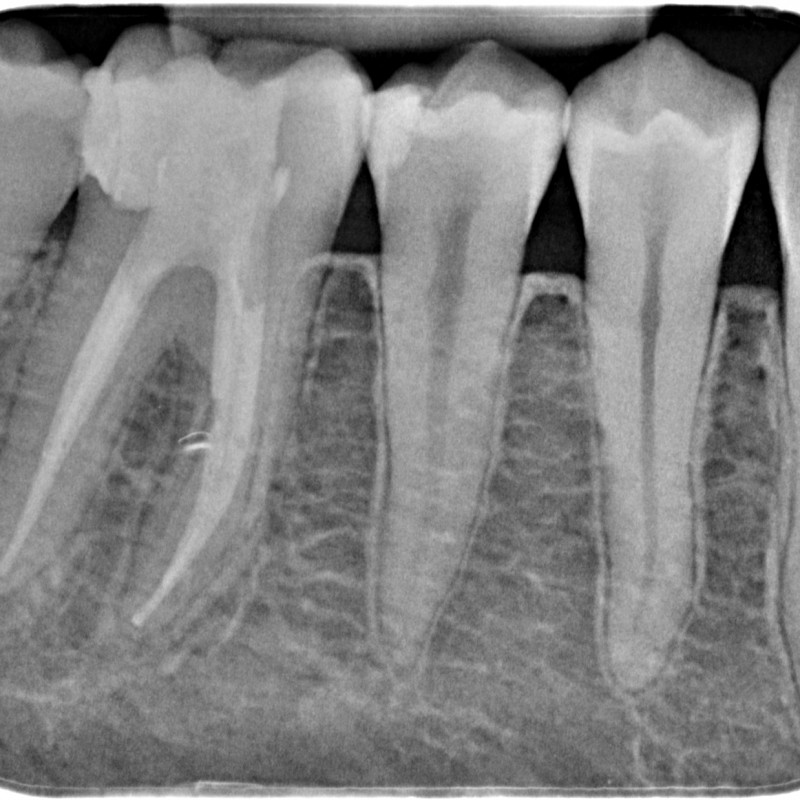

780613-05-5283-X-20150507-162045-XAFPNU2HWLK-4